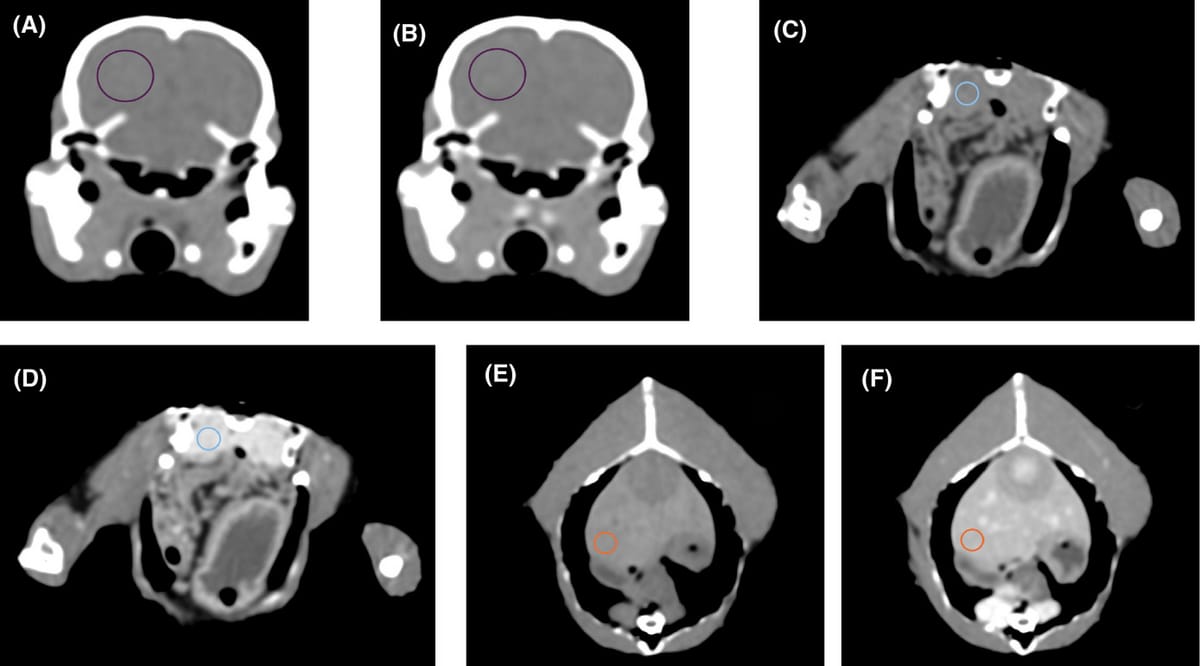

Representative CT images depicting regions of interest for the measurement of pre- and postcontrast Hounsfield units in both IV and IO studies (window level = 35 HU, window width = 360 HU, soft tissue reconstruction algorithm, 0.625 mm slice thickness). Pre (A) and post (B) transverse images at the level of the mid-calvarium with ROIs drawn over the brain. Pre (A) and post (B) transverse images at the level of the mid-celom with ROIs drawn over the liver. Pre (A) and post (B) transverse images at the level of the caudal celom with ROIs drawn over the right kidney